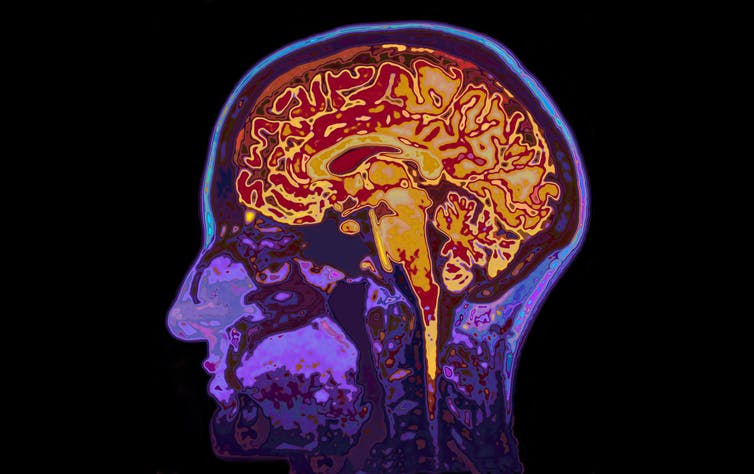

Beyin taramaları damarların çevresinde ve beynin beyaz maddesindeki değişimleri ortaya çıkardı.

Güney Kaliforniya Üniversitesi’nde Wilson Xu ile çalışan ekip şimdi migrenin yeni bir özelliğini keşfetti. Araştırma çerçevesinde kronik migren ağrısı çeken on kişinin, episodik migren atakları geçiren diğer on kişinin ve beş sağlıklı kişinin beyni yüksek çözünürlüklü beyin taramasıyla görüntülendi. Manyetik rezonans tomografisiyle alınan görüntülerde özellikle de kan damarlarının çevresindeki küçük değişimler dikkat çekiciydi. Araştırmacıları göre son çalışma, migren hastalarındaki mikrovasküler değişimlerin inceleyen ilk araştırma özelliğini taşıyor.

Bilim insanları migren ataklarının, beyindeki kan akışını etkileyerek, ağrılara neden olabileceğini uzun bir süredir tahmin ediyorlardı. Akut nöbetler dışında herhangi bir değişimin meydana gelip, gelmediğini öğrenmek isteyen Xu ve ekibi, incelemeler sonucunda kronik ve episodik migren ağrısı çeken kişilerin perivasküler alanlarında belirgin değişimler olduğunu fark etti. Bunlar beynin kan damarlarını çevreleyen ve lenflerin oluşmasında rol oynayan içleri sıvı dolu kanallar. Genişlemeleri bu damarlarda patolojik bir değişikliğin veya iltihaplanmanın bir göstergesi olabilir.

Analizlerden anlaşıldığı üzere migren hastalarında özellikle de Centrum semiovale denilen bölgedeki perivasküler alanlar genişlemiş. Korteks ve beynin ana ventrikülleri arasında yer alan bu beyin bölgesi, her şeyden önce sinir uçlarından oluşan beyaz maddeyi kapsar. Beynin iki yarımküresinde bulunan bu hilal şeklindeki alanda, araştırmacılar ayrıca kan kılcal damarlarındaki en küçük sızıntıların neden olduğu, çok sayıda küçük yoğunlaşmış alanlar ve mikro lezyonlar bulmuşlar.  Xu ve ekibine göre bu değişiklikler migrenin glifatik sistemdeki (atık ürünleri beyinden dışarı atan tübüller, boşluklar ve kanallar sistemi) bozulmasıyla alakalı olduğunu gösteriyor olabilir. Bununla birlikte tüm bu gözlemlerin migrenin bir sonucu mu olduğu yoksa nedeni mi olduğu kesin olarak bilinmiyor. Bilim insanları bu sorunun yanıtını, daha çok katılımlı ve daha uzun süreli araştırmalarla bulabilmeyi umuyorlar.